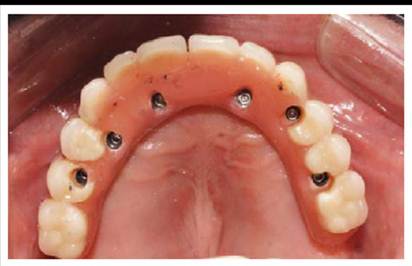

De acuerdo al protocolo reverso y al examen tomo-gráfico (Figura 2) con las guías multifuncionales mantuvimos la planificación inicial de realizar una prótesis híbrida superior implanto soportada sobre 6 implantes y 3 implantes en el maxilar inferior (Figura 3 ),

Debido a que en el maxilar superior se usó hueso liofilizado y al bajo torque del implante a nivel de la pieza 23 se esperó la oseointegración por 6 meses para proceder a la rehabilitación implantosoportada (3era fase). En el maxilar superior se probaron y torquearon los mini pilares CM , con un torque de 15N para mini pilares angulados y 32N para mini pilares rectos.

Se procedió a la transferencia de los pilares en el maxilar superior con cubeta abierta y ferulización de transfer (Figura 4), y a la transferencia de la plataforma de los implantes en el maxilar inferior.